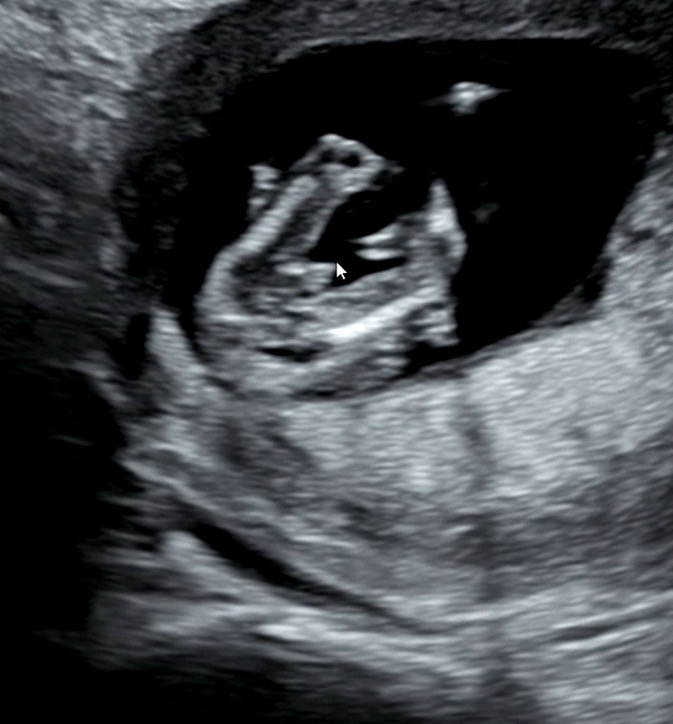

13주.. 이정도면 100프로 아들이겠죠..?

의사샘이 이정도면 바뀔 가능성은 없지만 한달뒤 진찰할 때 한번 더 보자구ㅋㅋㅋㅋㅋ ㅠㅠ 첫째는 딸일줄 알았는데 아들이라니 뭔가 실감이 안나지만 제발 나 안닮고 남편 닮았으면!!! ㅠㅠ해요ㅠㅠ

백퍼 아들입니다 저희애기도 춈파상 저랫어요

아 크기가 좀 애매하긴한데... 저희 첫찌 12주에 저렇게 있었다가 아들인 줄 알았는데 사라졌어요ㅎㅎㅎ 꼬리뼈였나봐요~

16주전에는 다 튀어나와있어서 모른다고 하던데용! 한달뒤에 다시볼거같아용

아들일듯여..ㅎㅎ 축하드려요!!